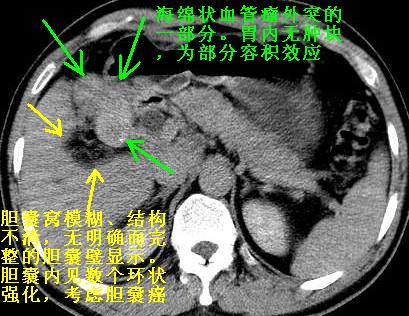

既然做了增强,为什么光提供延时期片子,肝动静脉期肝右叶前下段病灶增强如何?另外胆囊壁增厚,欠规整,内密度不均,与肝右叶病灶分界不清,增强表现怎样?肝内胆管轻度扩张,胆总管扩张,但未见明显结石影,也应提供增强早期图像才好鉴别扩张原因。片子较清,但不够完整,暂考虑1.胆囊癌肝局部浸润,或肝癌胆囊侵犯,2.胆总管下端或胰头钩突部占位。总之本人看不明白,请高手画图指示,先谢了!

由于胆囊窝内结构显示不清,肝脏病灶又邻近胆囊窝首先考虑胆囊癌肝受侵犯。而后因肝脏病灶强化有渐进改变,且相邻胆管扩张,故考虑肝胆管细胞癌待排。

胆总管及肝内胆管扩张,考虑是结石!但,肝内的低密度区增强不明,可能是肝ca,因为肝ca在增强时呈快进快出.另年胆总管扩张原因,可以考虑一下是不是,胆管ca.再次要考虑肝内的低密度是否为海绵状血管瘤所致!